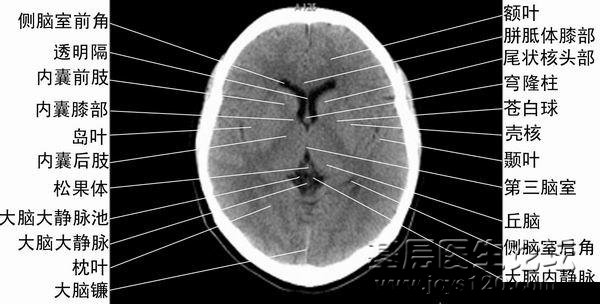

颅脑CT片详解